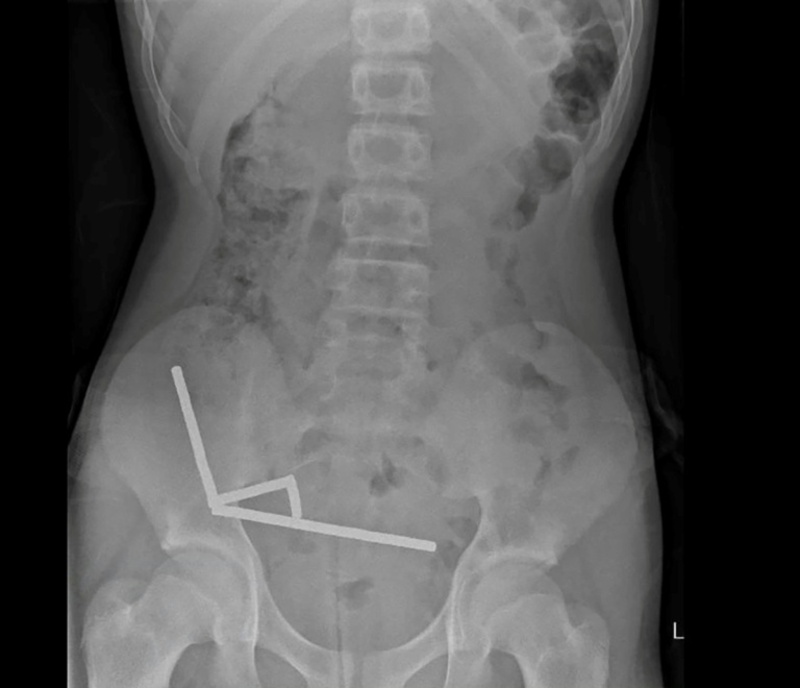

Neuseeland: Chirurgen entfernen bis zu 100 Magneten aus Gedärmen eines 13-Jährigen

Röntgenbild zeigt die Magneten im Unterleib des 13-Jährigen

Bild: AFP